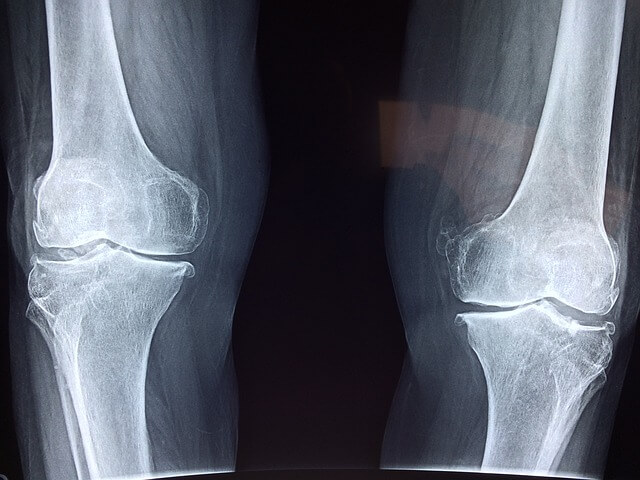

골격계 질환 중 많이 발생하는 골관절염

골관절염은 흔히 OA로 알려져 있으며, 전 세계 수백만 명에게 영향을 미치는 가장 흔한 형태의 관절염입니다. 관절의 연골이 점진적으로 분해되어 통증, 경직 및 이동성 저하를 초래하는 것이 특징인 퇴행성 관절 질환입니다. 이 절에서는 골관절염의 원인, 위험 요인, 증상, 진단 및 치료 옵션을 탐구하면서 골관절염의 복잡성을 탐구할 것입니다. 골관절염의 정확한 원인은 다인성으로 유전적, 환경적, 기계적 요인이 복합적으로 작용합니다. 연골은 시간이 지남에 따라 자연적으로 퇴화되기 때문에 노화는 주요 위험 요소입니다. 다른 위험 요소로는 관절 부상이나 외상, 비만, 직업이나 스포츠로 인한 관절의 반복적인 스트레스, 유전적 소인, 관절 정렬 이상이나 대사 장애와 같은 특정한 의학적 조건이 있습니다. 골관절염은 일반적으로 관절 통증, 경직, 관절 가동 범위 감소와 같은 증상을 보이며, 특히 운동을 하지 않거나 과다 사용한 기간 이후에 나타납니다. 가장 일반적으로 영향을 받는 관절은 무릎, 엉덩이, 손, 척추를 포함합니다. 골관절염이 진행됨에 따라 개인은 관절 부종, 압통 및 골 혹(골다공증)의 형성을 경험할 수 있습니다. 심한 경우 골관절염은 관절 기형, 장애 및 삶의 질 저하를 초래할 수 있습니다. 골관절염을 진단하기 위해서는 병력, 신체 검사, 영상 연구(X-ray 또는 자기 공명 영상과 같은), 그리고 다른 상태들을 배제하기 위한 실험실 테스트의 조합이 포함됩니다. 치료 전략은 증상을 완화하고, 관절 기능을 개선하며, 질병의 진행을 늦추는 것을 목표로 합니다. 여기에는 체중 관리, 운동, 물리 치료, 보조 장치(예: 교정기 또는 부목), 그리고 열 또는 감기 치료와 같은 비약리학적 개입의 조합이 포함될 수 있습니다. 또한 통증과 염증을 관리하기 위해 진통제(통증 완화제), 비스테로이드성 소염제(NSAID), 코르티코스테로이드 주사 또는 점액 보충제와 같은 약물이 처방될 수 있습니다. 골관절염은 영향을 받는 개인의 삶에 중대한 영향을 미치는 만연하고 쇠약한 상태입니다. 골관절염의 원인, 위험 요소, 증상, 진단 및 치료 옵션을 이해함으로써 개인은 자신의 상태를 관리하고 삶의 질을 향상시키기 위해 사전 조치를 취할 수 있습니다. 생활 양식 수정, 의료 개입 및 지속적인 지원을 포함하는 다학제적 접근을 통해 골관절염의 부담을 최소화하여 이 만성 관절 질환으로 인한 어려움에도 불구하고 개인이 능동적이고 만족스러운 삶을 살 수 있습니다.